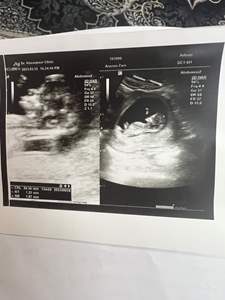

سؤال احتمال 70 درصد سونوی NT گفت دختره... درسته؟